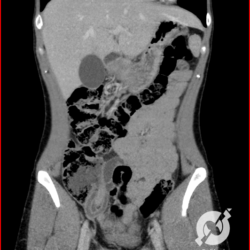

Aqui uma reconstrução coronal de uma tomografia do abdome para investigação de um indivíduo jovem com dor abdominal baixa, mais à ESQUERDA. O diagnóstico clínico era de cólica renoureteral esquerda. Fica bem evidente a imagem do apêndice no seu maior eixo, com paredes espessas e densificação inflamatória adiposa circunjacente. Reparem, no entanto, que a extremidade apendicular está situada à esquerda da linha média, daí o quadro clínico ser deste lado.